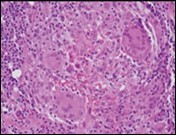

Core needle biopsy of idiopathic granulomatous mastitis enunciates multiple aggregates of non- caseating epitheloid cell granulomas within and encompassing breast lobules, constituted of epitheloid histiocytes, lymphocytes, neutrophils and multinucleated giant cells. Granulomatous inflammation is predominantly lobulo-centric. The inflammation is preponderantly composed of lymphocytes, plasma cells, epitheloid histiocytes, multinucleated giant cells and neutrophils. Neutrophils can configure micro-abscesses and encompass vacant micro-cystic cavities, morphological features which are in common with cystic neutrophilic granulomatous mastitis. Non specific lobulitis along with a lymphoid and plasma cell infiltrate accompanies the granulomatous inflammation. Necrosis is usually absent. Neutrophilic micro-abscesses can be accompanied by fistula formation 4, 5.

Multinucleated giant cells are detected in an estimated three fourths (78.5%) instances. Plasma cells are discernible in around half (53.9%) of the subjects and usually appear at the margins of cystic vacuoles with centric accumulation of neutrophils within the granulomas.

Figure 1.Granulomatous mastitis with the configuration of epitheloid cell granuloma and a lymphoid and plasma cell infiltrate9.

Figure 2.Granulomatous mastitis with articulated epitheloid cell granuloma, lymphocytic, plasma cell and neutrophilic infiltration10.